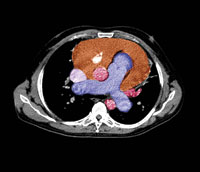

Inflammatoriske mekanismer antas å ligge bak sen postoperativ perikardial effusjon hos hjertepasienter, men diklofenak forebygger ikke hjertetamponade.

Perikardial effusjon er vanlig etter hjertekirurgi og kan utvikle seg til hjertetamponade. Pasienter med vedvarende perikardial effusjon gis ofte ikke-steroidale antiinflammatoriske legemidler (NSAID), men det foreligger ingen dokumentasjon på effekten av slik behandling.

I en fransk multisenterstudie ble 196 pasienter med moderat til uttalt perikardial effusjon mer enn sju dager etter hjertekirurgi randomisert til enten diklofenak 50 mg eller placebo to ganger daglig i 14 dager (1). Effusjonen ble redusert omtrent like mye i begge gruppene. Omtrent like mange i hver gruppe utviklet hjertetamponade, henholdsvis ni og 11 pasienter (p = 0,64). Justeringer for effusjonsgrad, sykehus og type hjertekirurgi endret ikke resultatene.